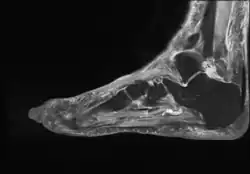

The diagnosis of bursitis can be done via a musculoskeletal ultrasound[5]

- Achilles bursitis

- Retrocalcaneal bursitis